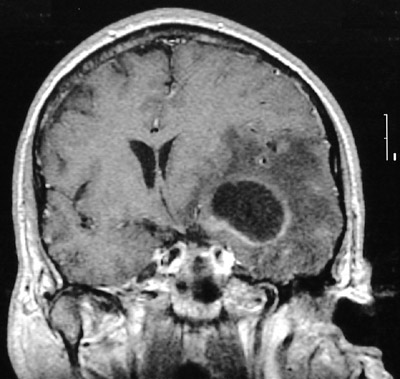

This MRI scan in coronal view demonstrates a

cerebral abscess

. There is

cerebral edema

. The mass effect has resulted in a

midline shift to the right

. Aspergillus was cultured.